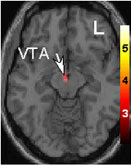

Básicamente, buscar cuáles eran las bases neuroanatómicas que se activan en el estado de enamoramiento. Esto fue lo que encontraron

Esa pequeña zona en la base del cerebro se llama “área ventral tegmetal”, en la cual encontraron actividad de las células APEN, células que producen dopamina y que la rocían en muchas partes del cerebro. Esta zona es parte del sistema de gratificación del cerebro, zona asociada al deseo, motivación, enfoque y ansias; también es la zona que se activa en las personas adictas, por ejemplo, a la cocaína. Sí, el amor romántico es una adicción, y lo terrible de este sistema de gratificación para muchos, es que cuando no podemos acceder a aquello que queremos, trabaja con más intensidad, es decir, que la ansiedad, la obsesión y la desesperación por aquello que queremos, es más fuerte.